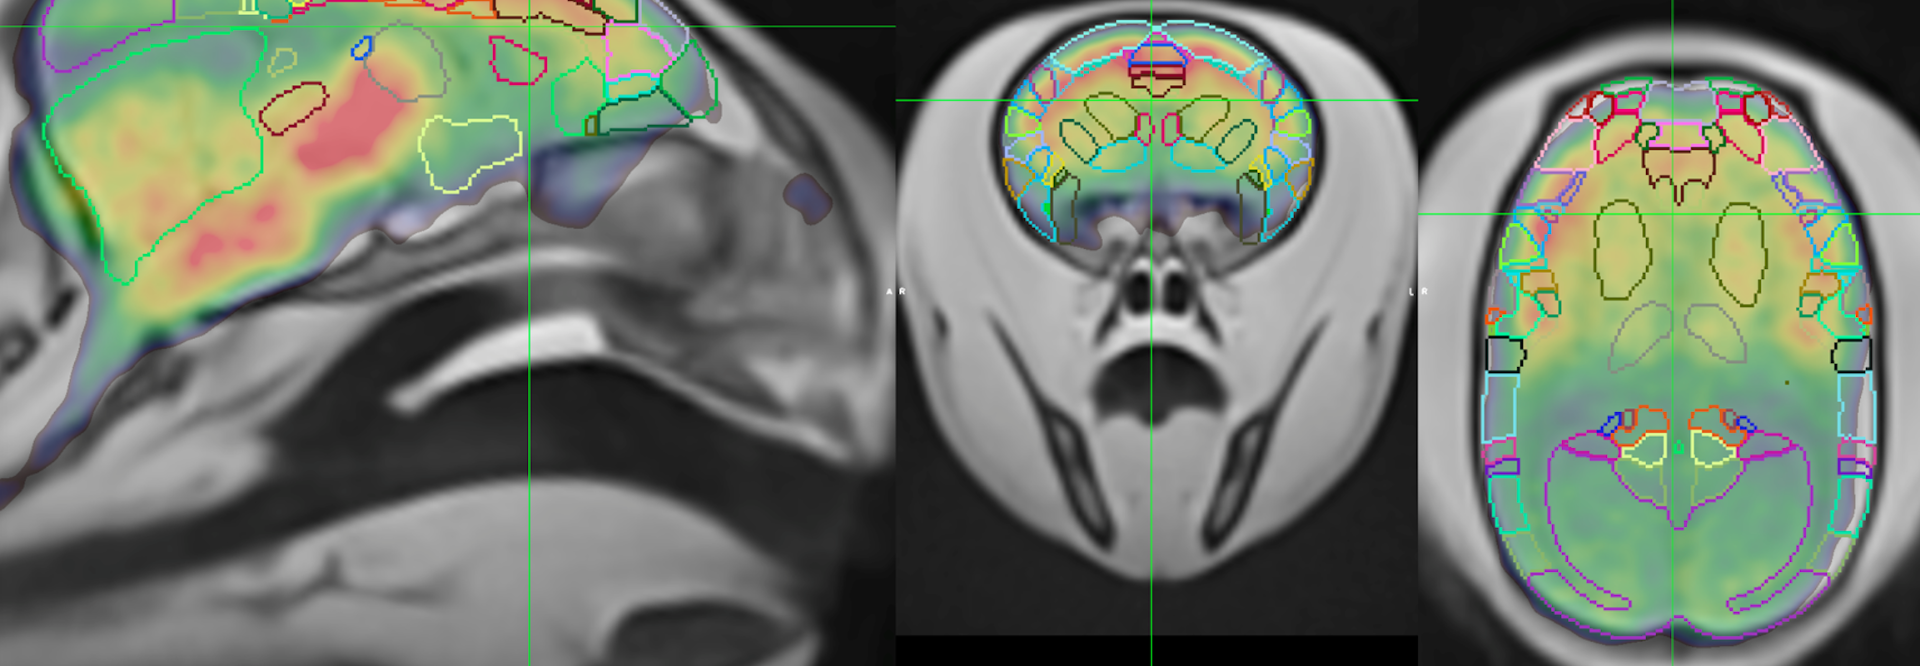

We are working to establish the marmoset as the first primate-specific model to reveal the earliest cellular and molecular events of AD processes and allow charting of AD progression from its inception. We believe that the simultaneous assessment of genetic, molecular, functional, behavioral, and pathological phenotypes in marmosets will provide translatable knowledge of the origins and progression of AD in human populations. In this webinar, I will describe our use of multimodal neuroimaging techniques to evaluate AD-related phenotypes in our marmoset AD models, carrying all imaging in conscious, fully awake animals, thus avoiding the confounds of anesthesia.